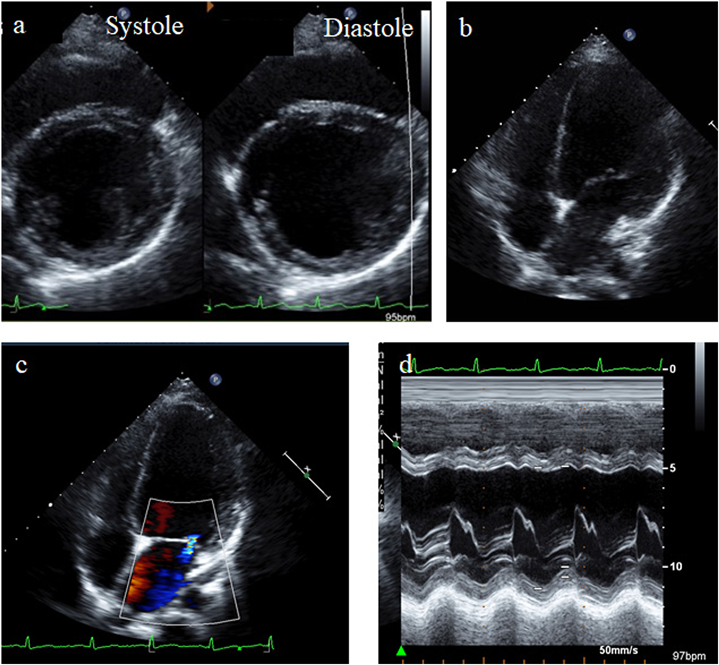

Chest X-ray showed cardiac enlargement with the cardiothoracic ratio of 53% (Fig. 1a). Electrocardiogram showed poor R wave progression and the corrected QT interval was 436 ms (Fig.1b). Echocardiography showed dilated left ventricular size (Fig. 2a, b) with an end diastolic diameter of 65.0 mm (Z-score +3.58), moderate mitral valve regurgitation (Fig.2c), and left ventricular ejection fraction of 35% (Fig. 2d). These findings were compatible with DCM.

Fig. 2 Echocardiography of the present case at initial evaluation. (a) Dilatation of the left ventricle and impaired left ventricular systolic function were demonstrated. (b) The apical four-chamber view showed the enlarged left ventricle. (c) The color doppler image of the apical four-chamber view demonstrated mild mitral regurgitation. (d) The image of M-mode of left ventricle showed impaired left ventricular systolic function